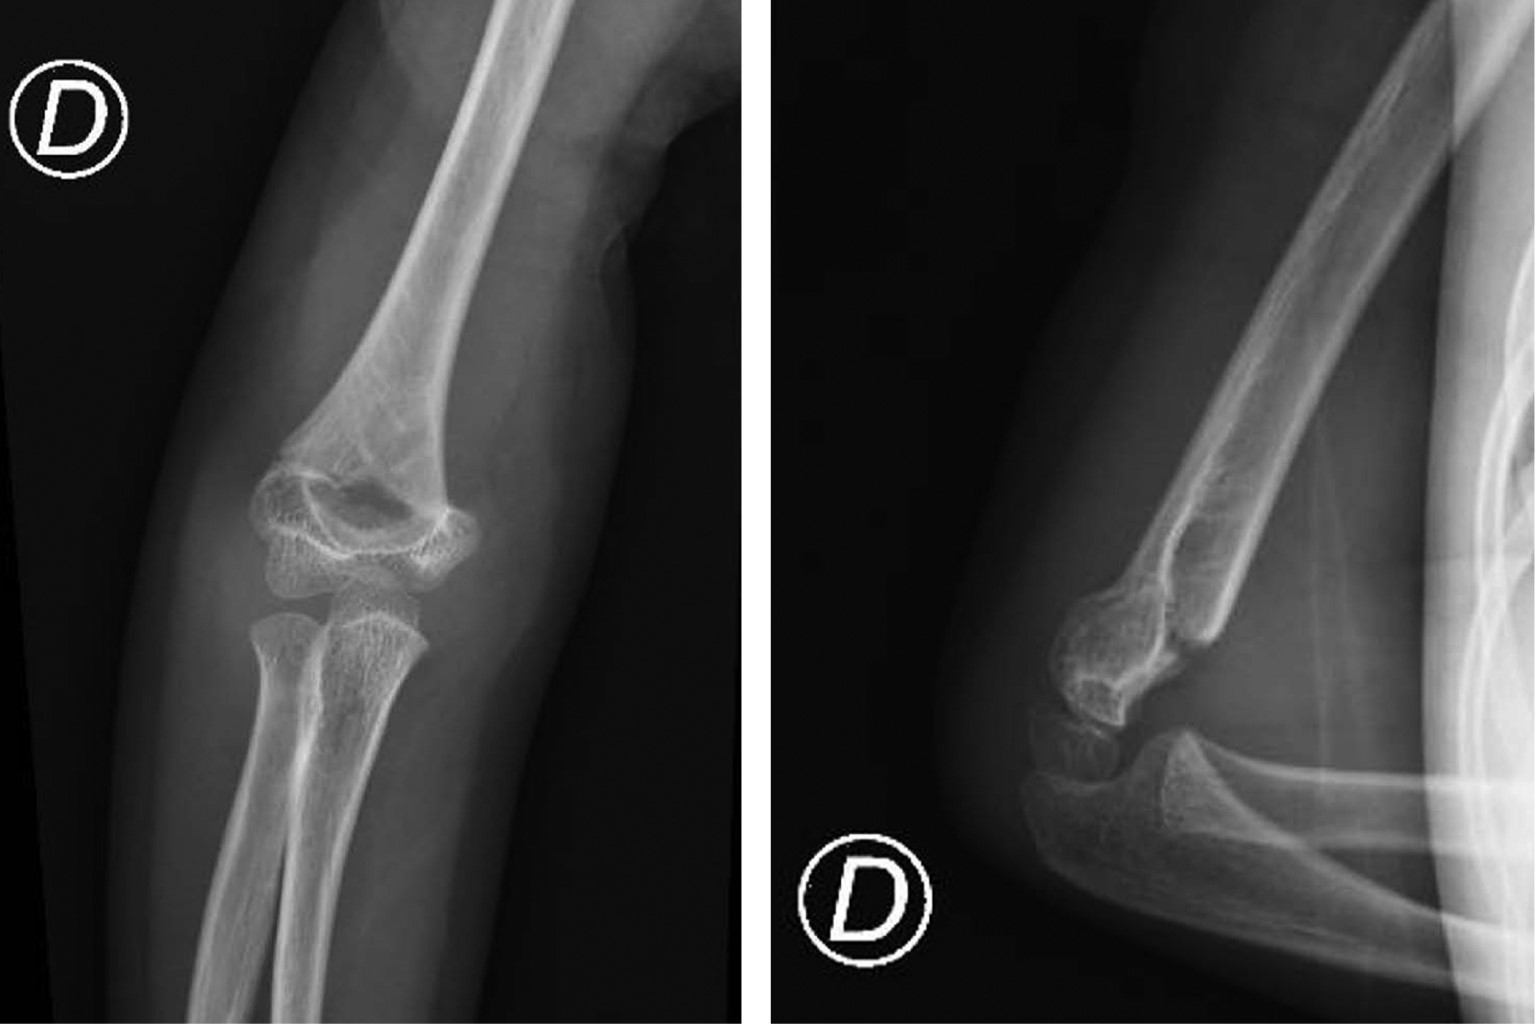

CASO 4

Femenino seis años – Fractura supracondílea Gartland II sin lesión neurovascular (Figura 4).

• 1. Tratamiento conservador – Dr. Sergio Martínez Álvarez (SEOP):

• 2. Reducción cerrada y enclavijado percutáneo – Dra. Valeria Amelong (SAOTI):